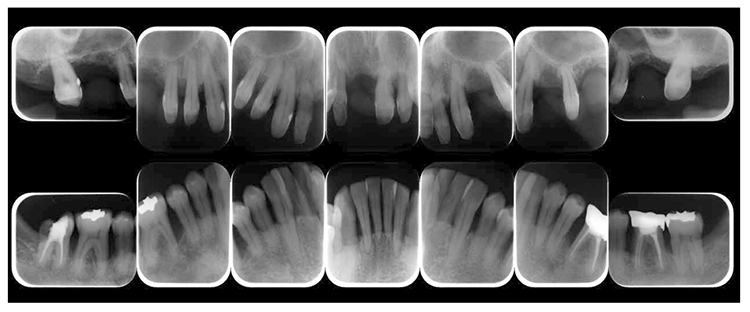

(3) X-ray findings

At the first visit, the findings showed moderate to advanced horizontal alveolar bone resorption in the entire jaw, and advanced vertical bone resorption on 24,36,46, 47. Additionally, on 46,47 were radiolucent findings that were likely associated with furcation involvement, and radiolucent areas on the alveolar bone surrounding the root apex were shown on 16,11,26. Furthermore, distally on 47, radiolucent findings showed caries extending into the dental pulp.(Fig.1c).

(Fig.1c) Dental X-ray 14 during first visit (June 2007)